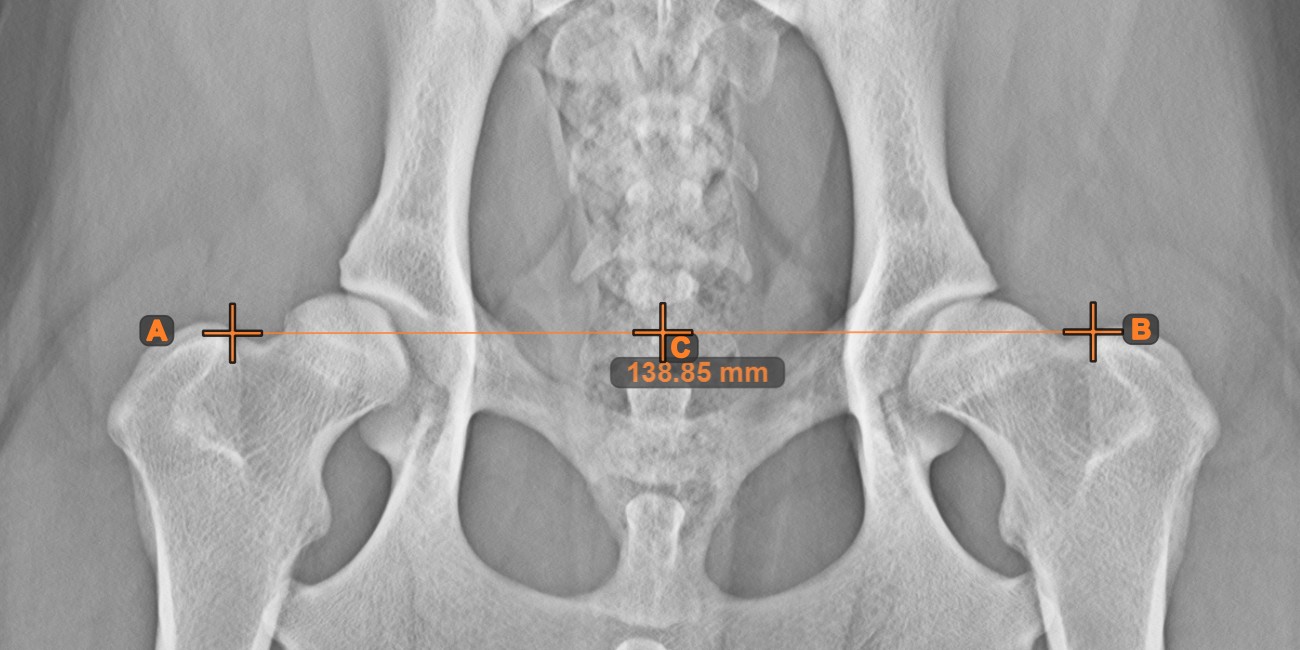

Center Point of Line¶

Identify and mark the center point of a new or existing line measurement on the scene by using the Center Point of Line

tool.

Select the tool from the left toolbar and assign it to one of the available mouse buttons. Place the start and end points on the scene, select them from already existing points on the image, or select an already drawn line from the scene. The center point of the line will be automatically calculated and placed on the scene. The center point of each line will always be marked with the letter C.